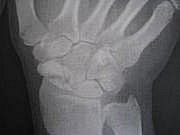

二日ぶりのコンニチワです。 20日水曜日に予定どうりにオペに挑みました。 病室からオペ室まで看護師さんと話をしながら歩いていきました。 周りから見るとどこが悪いの??って思われそうです(笑) 手術は何度もありますが全身麻酔は始めての経験なので 多少の不安はありましたが・・ありゃ凄い...